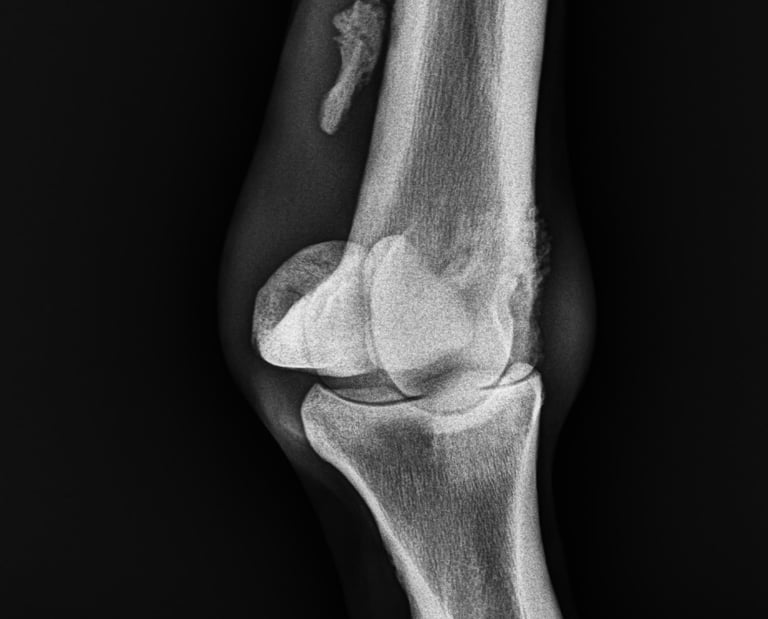

DIAGNOSTICO POR IMAGENES: ECOGRAFIA Y RADIOGRAFIA